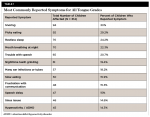

The most commonly reported symptoms for the entire sample of children were snoring (30%), picky eating (29.3%), restless sleep (24.2%), mouth breathing at night (22.3%), trouble with speech sounds (20.7%), grinding teeth at night (19.4%), ear tubes or many ear infections (18.2%), slow eating (15.9%), frustration with communication (15.3%), speech delay (15%), sinus issues (14.6%), and hyperactivity or attention deficit hyperactivity disorder (ADHD) (14.3%) (Table 1).